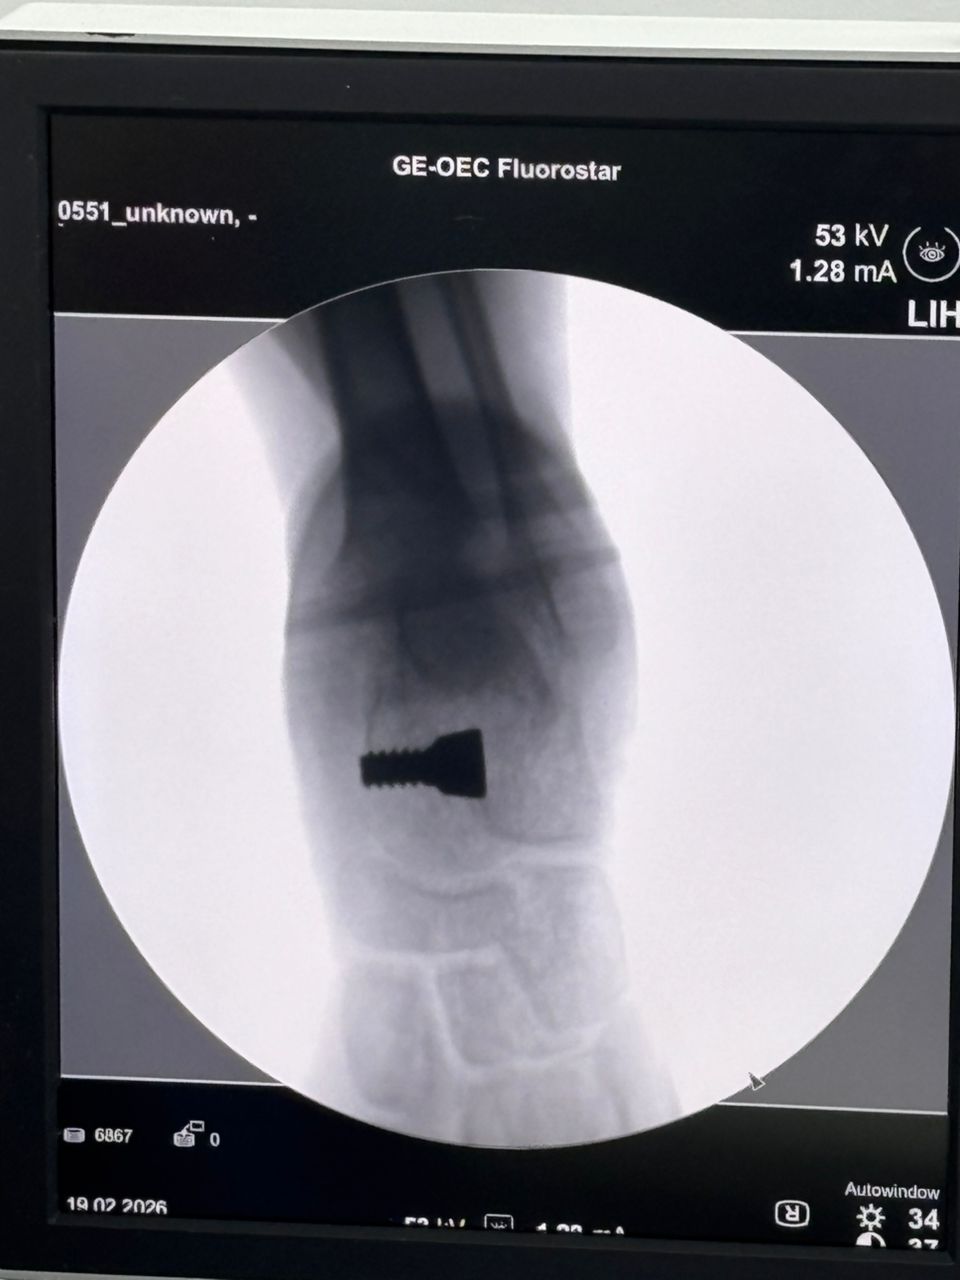

Fulkerson